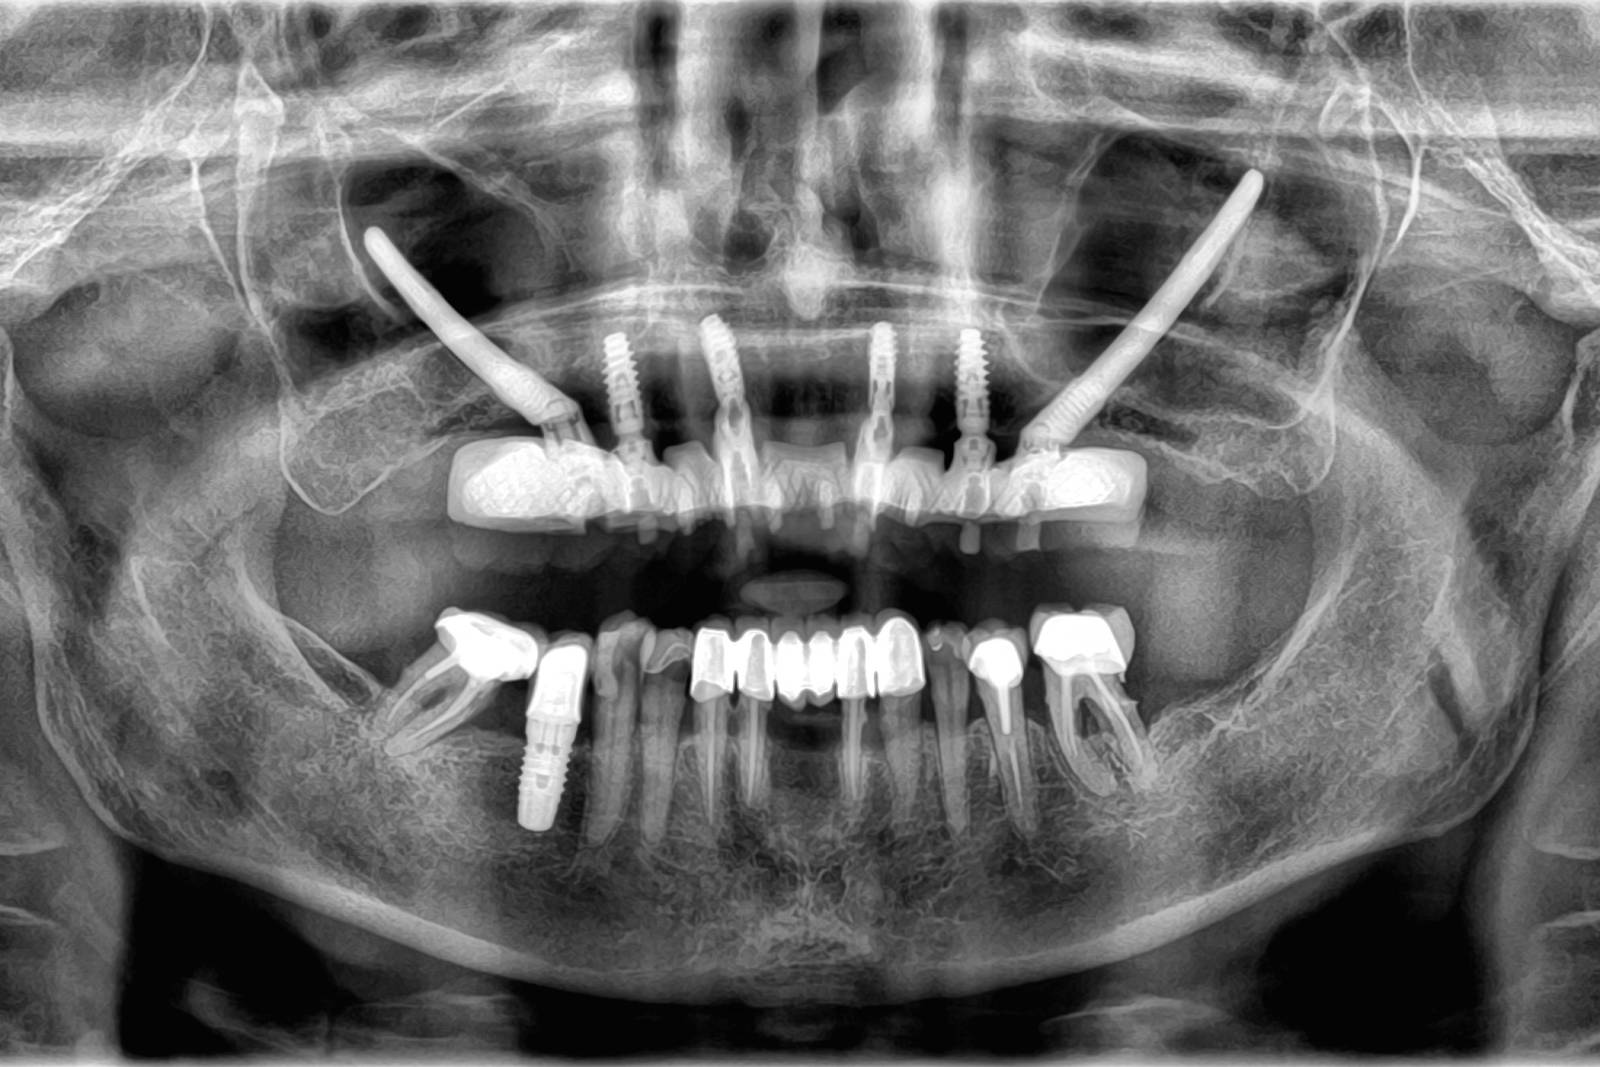

L'implant zygomatique, également connu sous le nom d'implant malaire, est une option de traitement utilisée au cabinet Implantys près de Mâcon pour ancrer des prothèses dentaires chez les patients qui ont une perte osseuse sévère dans la région maxillaire supérieure et qui ne peuvent pas bénéficier d'implants conventionnels en raison du manque de densité osseuse. L'implant zygomatique diffère donc des implants dentaires conventionnels qui sont, eux, insérés dans l'os maxillaire. Cet implant est conçu pour être fixé dans l'os zygomatique, également appelé os malaire, situé près de la pommette. Cette alternative vous est proposée par nos chirurgiens dentistes spécialisés en implantologie, au cabinet Implantys proche de Belleville-en-Beaujolais.

Le processus d'implantation zygomatique est plus complexe que celui des implants conventionnels. Il nécessite une évaluation et une planification approfondies, ainsi qu'une intervention chirurgicale réalisée par un spécialiste qualifié, comme vous en trouverez dans notre au cabinet Implantys près de Belleville-en-Beaujolais. Pendant la chirurgie réalisée sous anesthésie générale, l'implant zygomatique est fixé à l'os zygomatique de manière à fournir une base solide pour les prothèses dentaires, telles que les bridges ou les prothèses complètes.